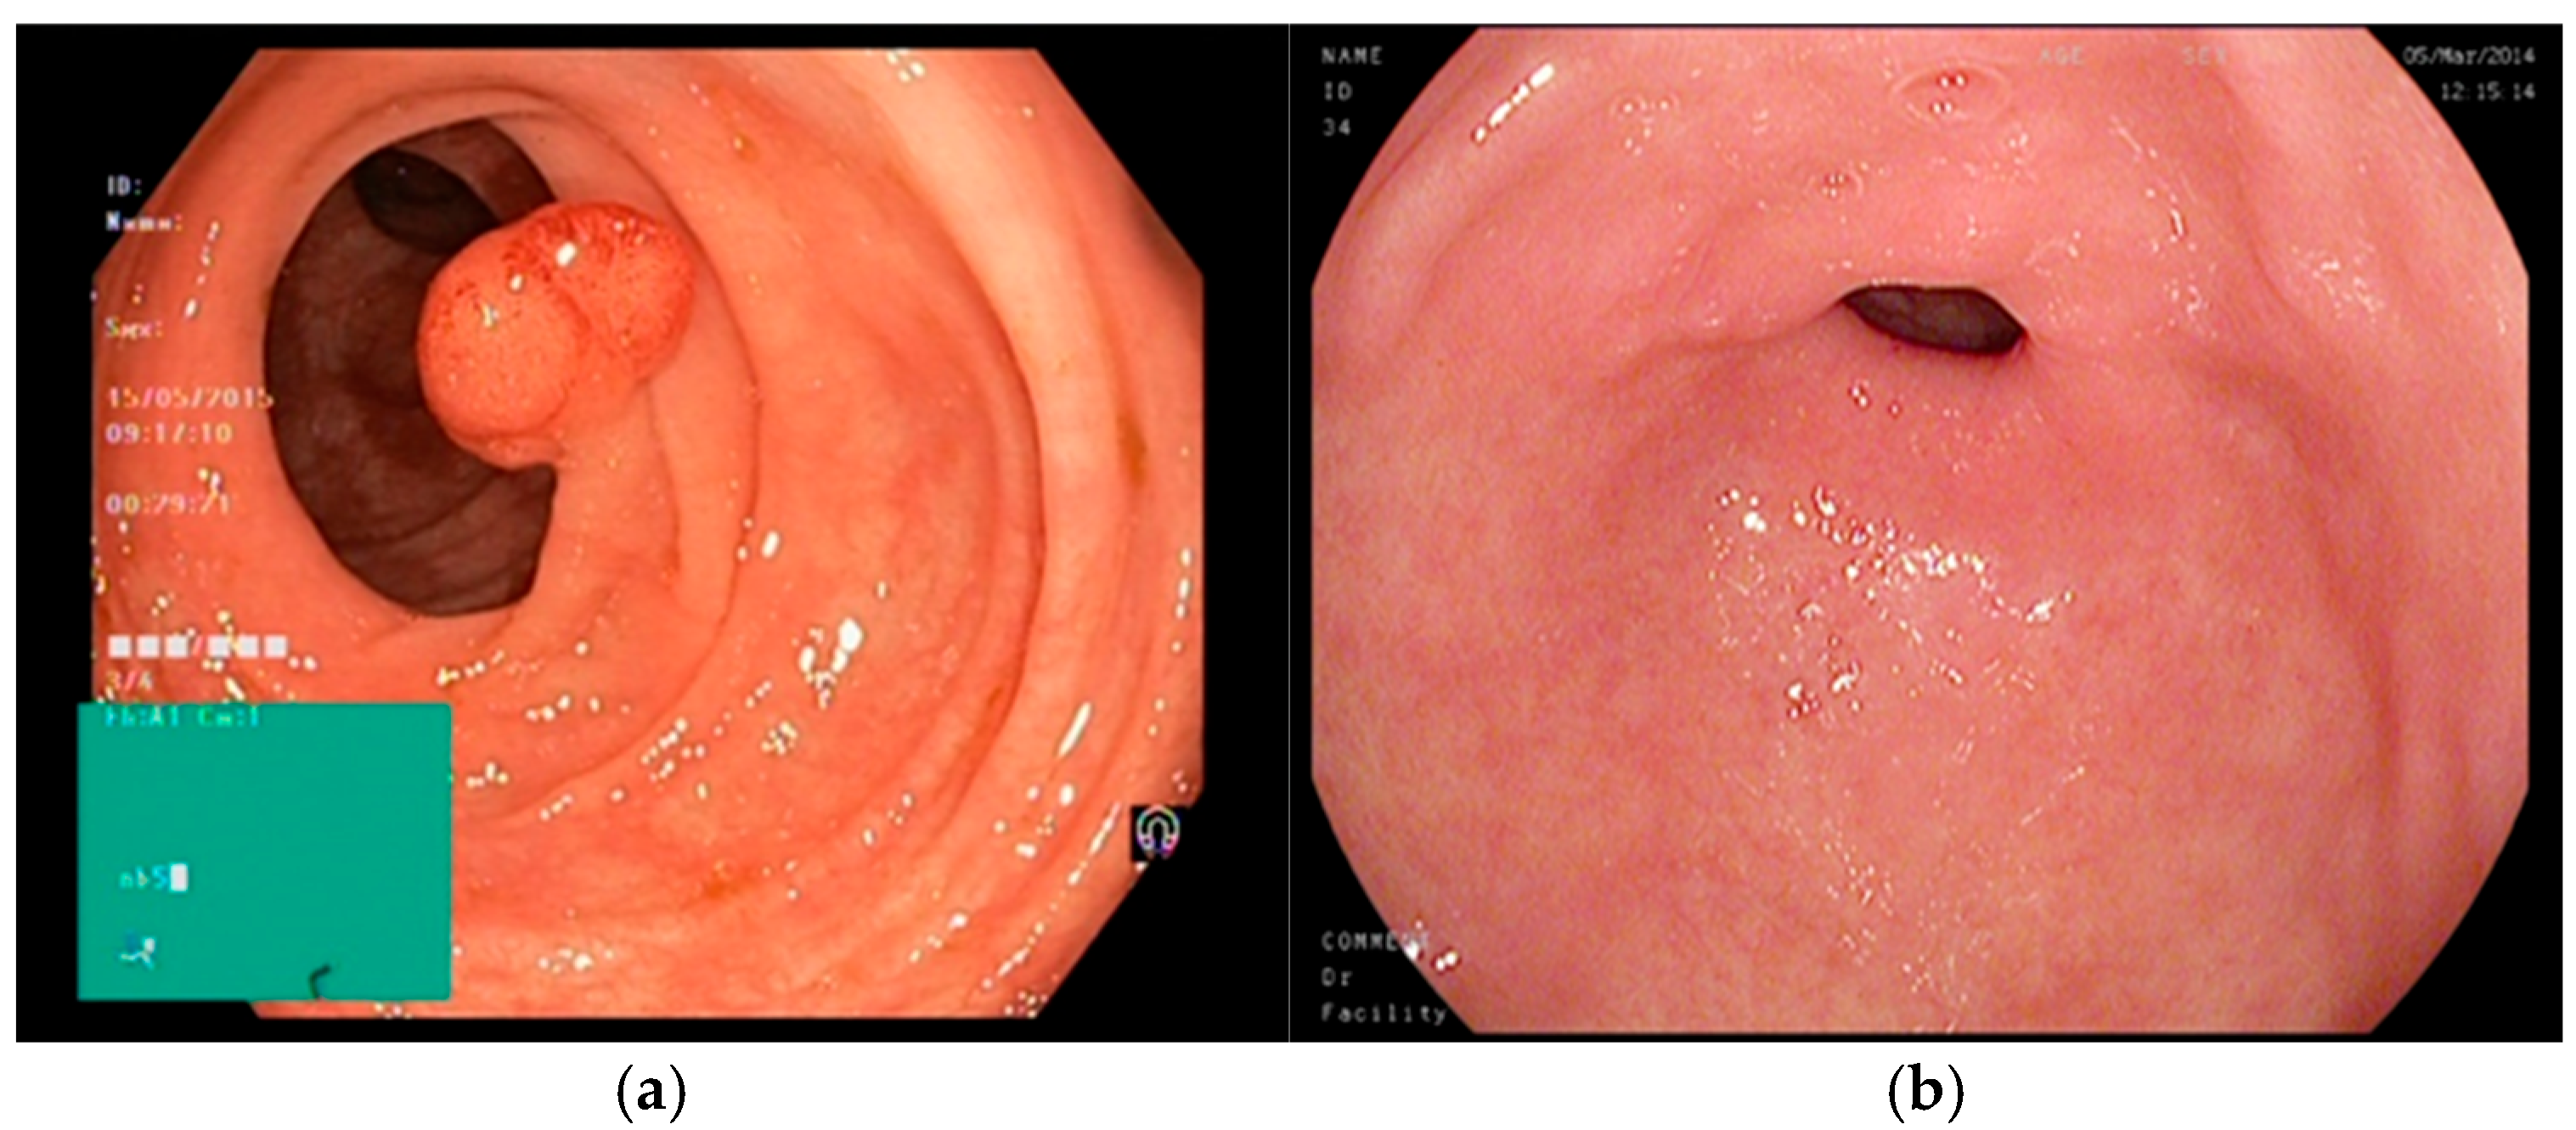

| Case | Dataset | Total Images | Healthy | Polyp | Ulcer |

|---|---|---|---|---|---|

| 3 possible labels | Initial | 1200 | 400 | 400 | 400 |

| Augmented | 4800 | 1600 | 1600 | 1600 | |

| 2 possible labels | Initial | 800 | 400 | 400 | 0 |

| Augmented | 3200 | 1600 | 1600 | 0 |